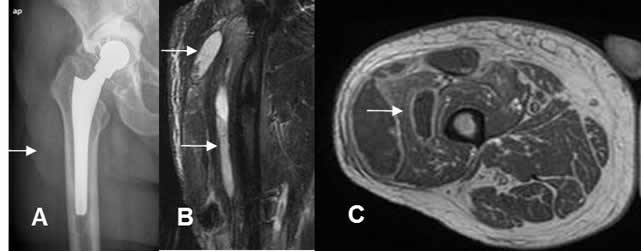

Fig 136 B. Infección postquirúrgica.

A: Rx AP. Prótesis de la cabeza femoral, por fractura basicervical. Se encuentra prominencia en los tejidos blandos.

B: RM coronal en STIR y C: RM axial en T1 con contraste. Edema de tejidos blandos, con colecciones líquidas cuyos bordes realzan con el contraste, por la formación de abscesos.